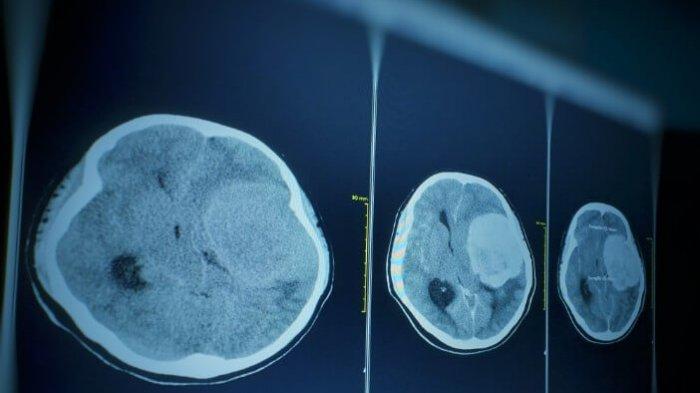

TRIBUNNEWSWIKI.COM - Neuroma akustik adalah tumor jinak yang tumbuh pada saraf keseimbangan (vestibular) yaitu saraf menghubungkan bagian dalam telinga dengan otak.

Tumor otak ini disebut juga dengan vestibular schwannoma karena tumbuh dari sel Schwann, sel yang menutupi saraf keseimbangan.